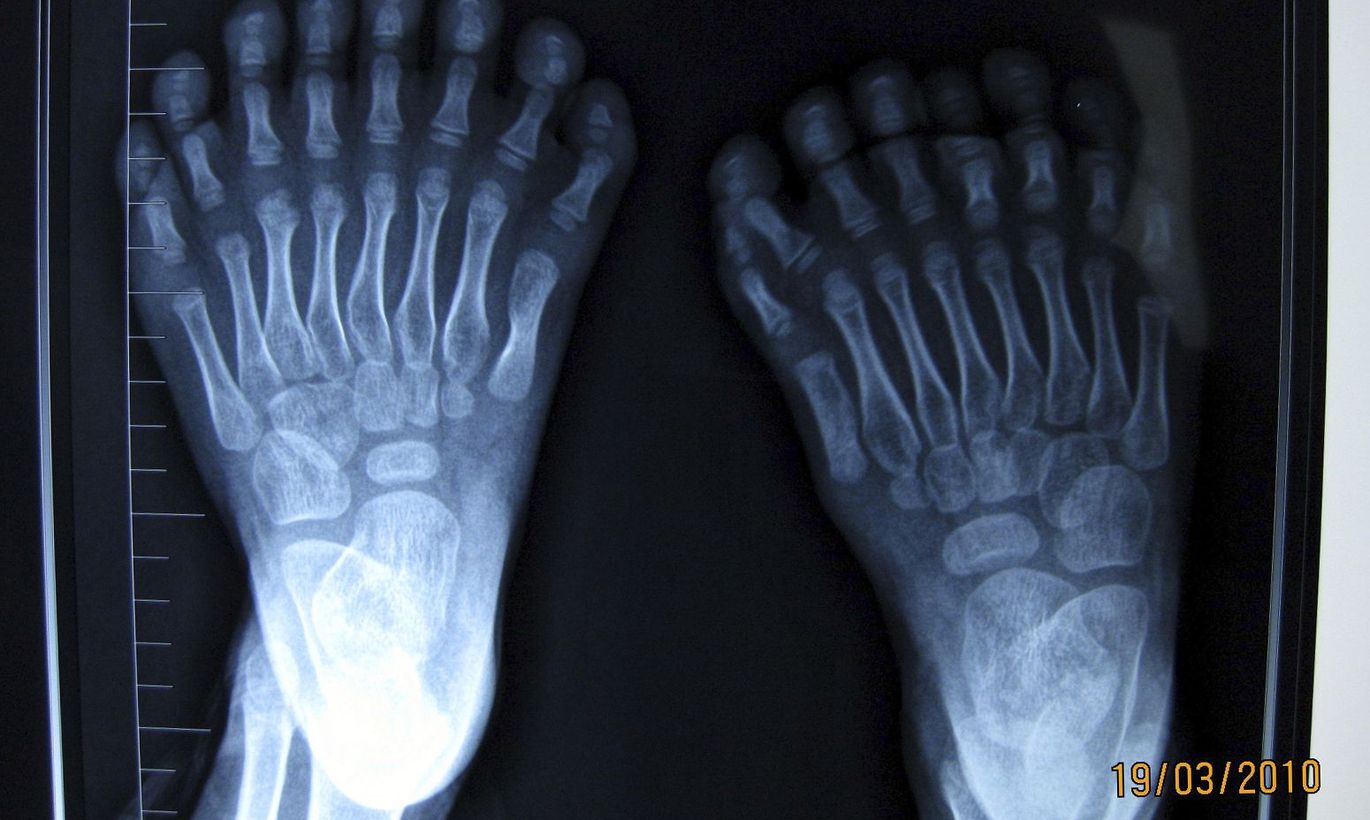

6 Пальцев На Ноге Фото